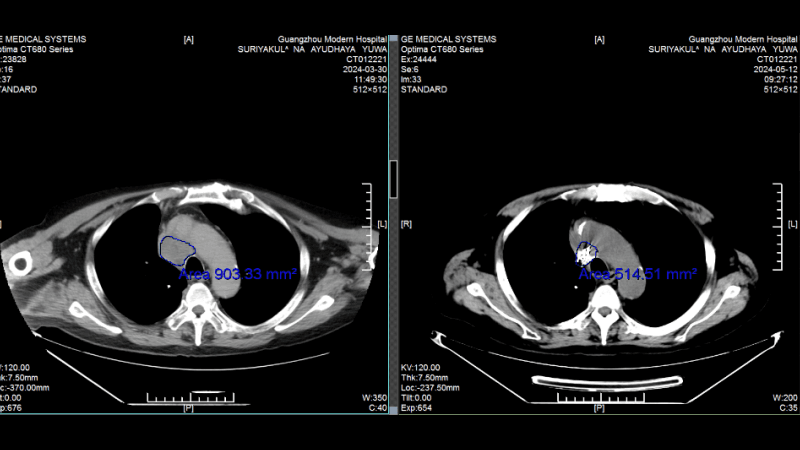

Малоинвазивная интервенционная терапия помогла победить синхронный рак легкого и колоректальный рак, когда хирурги всего мира предлагали только калечащие операцииИстория пациента: Радик, 63 года, Россия. Диагноз: Два первичных очага: плоскоклеточный рак легкого и аденокарцинома прямой кишки (синхронный рак). Тактика лечения: Курс интервенционной терапии (химоэмболизация). Результат: Очаг в легком практически неактивен, опухоль в кишечнике уменьшилась на 90%. Полное восстановление качества жизни.

Сравнение КТ лёгких до и после лечения. Опухоль лёгких практически инактивирована

(Слева: до лечения, справа: после лечения)

Лечение дало ошеломляющие результаты: • После двух процедур КТ показало уменьшение очага в легком, а колоноскопия - значительное сокращение опухоли в кишечнике. • Исчезли мучительные симптомы: кашель и кровавый стул. • После семи сеансов опухоль в легком была практически полностью инактивирована, а в кишечнике - уменьшилась на 90%. Путь не был усыпан розами. Однажды у Радика резко упал уровень тромбоцитов, что грозило опасным кровотечением. В момент отчаяния именно настойчивость и профессионализм его лечащего врача, доктора Аденана, и всей команды спасли ситуацию. Быстро проведенная симптоматическая терапия стабилизировала состояние, и лечение было продолжено.